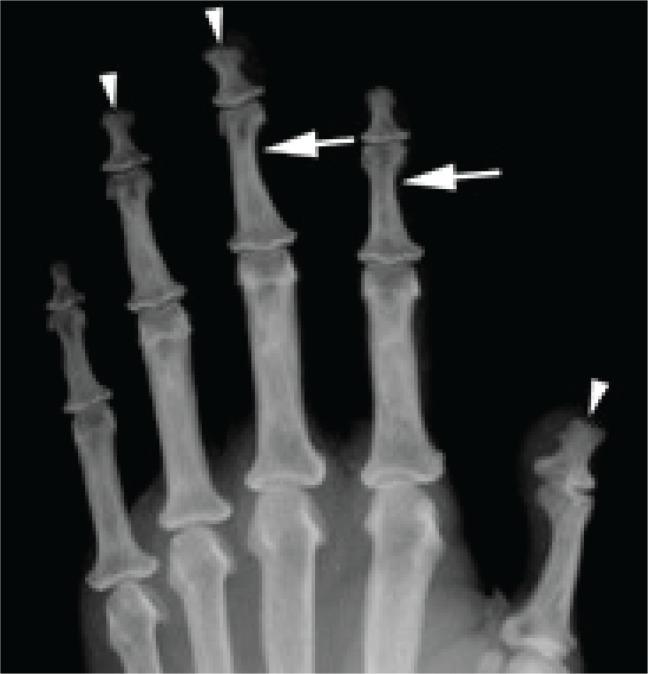

We present the rare case of a 47-year-old woman with protracted primary hyperparathyroidism complicated by communicating hydrocephalus and cerebellar tonsillar herniation secondary to calvarial thickening. The parathyroid glands remained elusive, despite the use of advanced preoperative imaging modalities and three neck explorations. The serum calcium was optimally controlled with cinacalcet and alfacalcidol. Awareness of this rare complication is essential for early diagnosis and prompt intervention to prevent fatal posterior brain herniation.